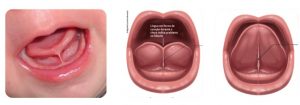

- logo após o nascimento o bebê fizer o TESTE DA LINGUINHA por um profissional capacitado,

Porém, é claro que com parcimônia, afinal sem dente não há cárie e o objetivo nessa fase é outro, mas que tal olhar um pouquinho para a linguinha.